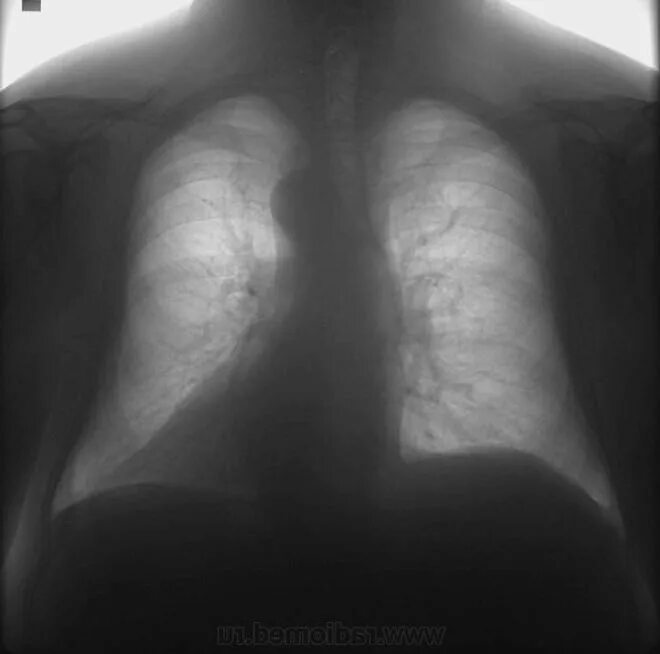

Как выглядит фиброз легких